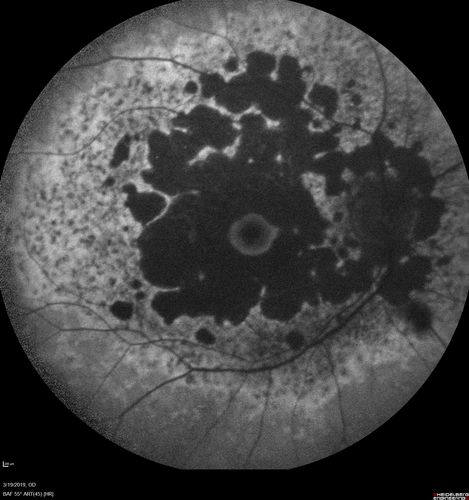

Concentric Geographic Atrophy - 76 year old man

Gradual vision loss, worse at night. VA 20/40 OU.

Concentric Geographic Atrophy - 76 YO male